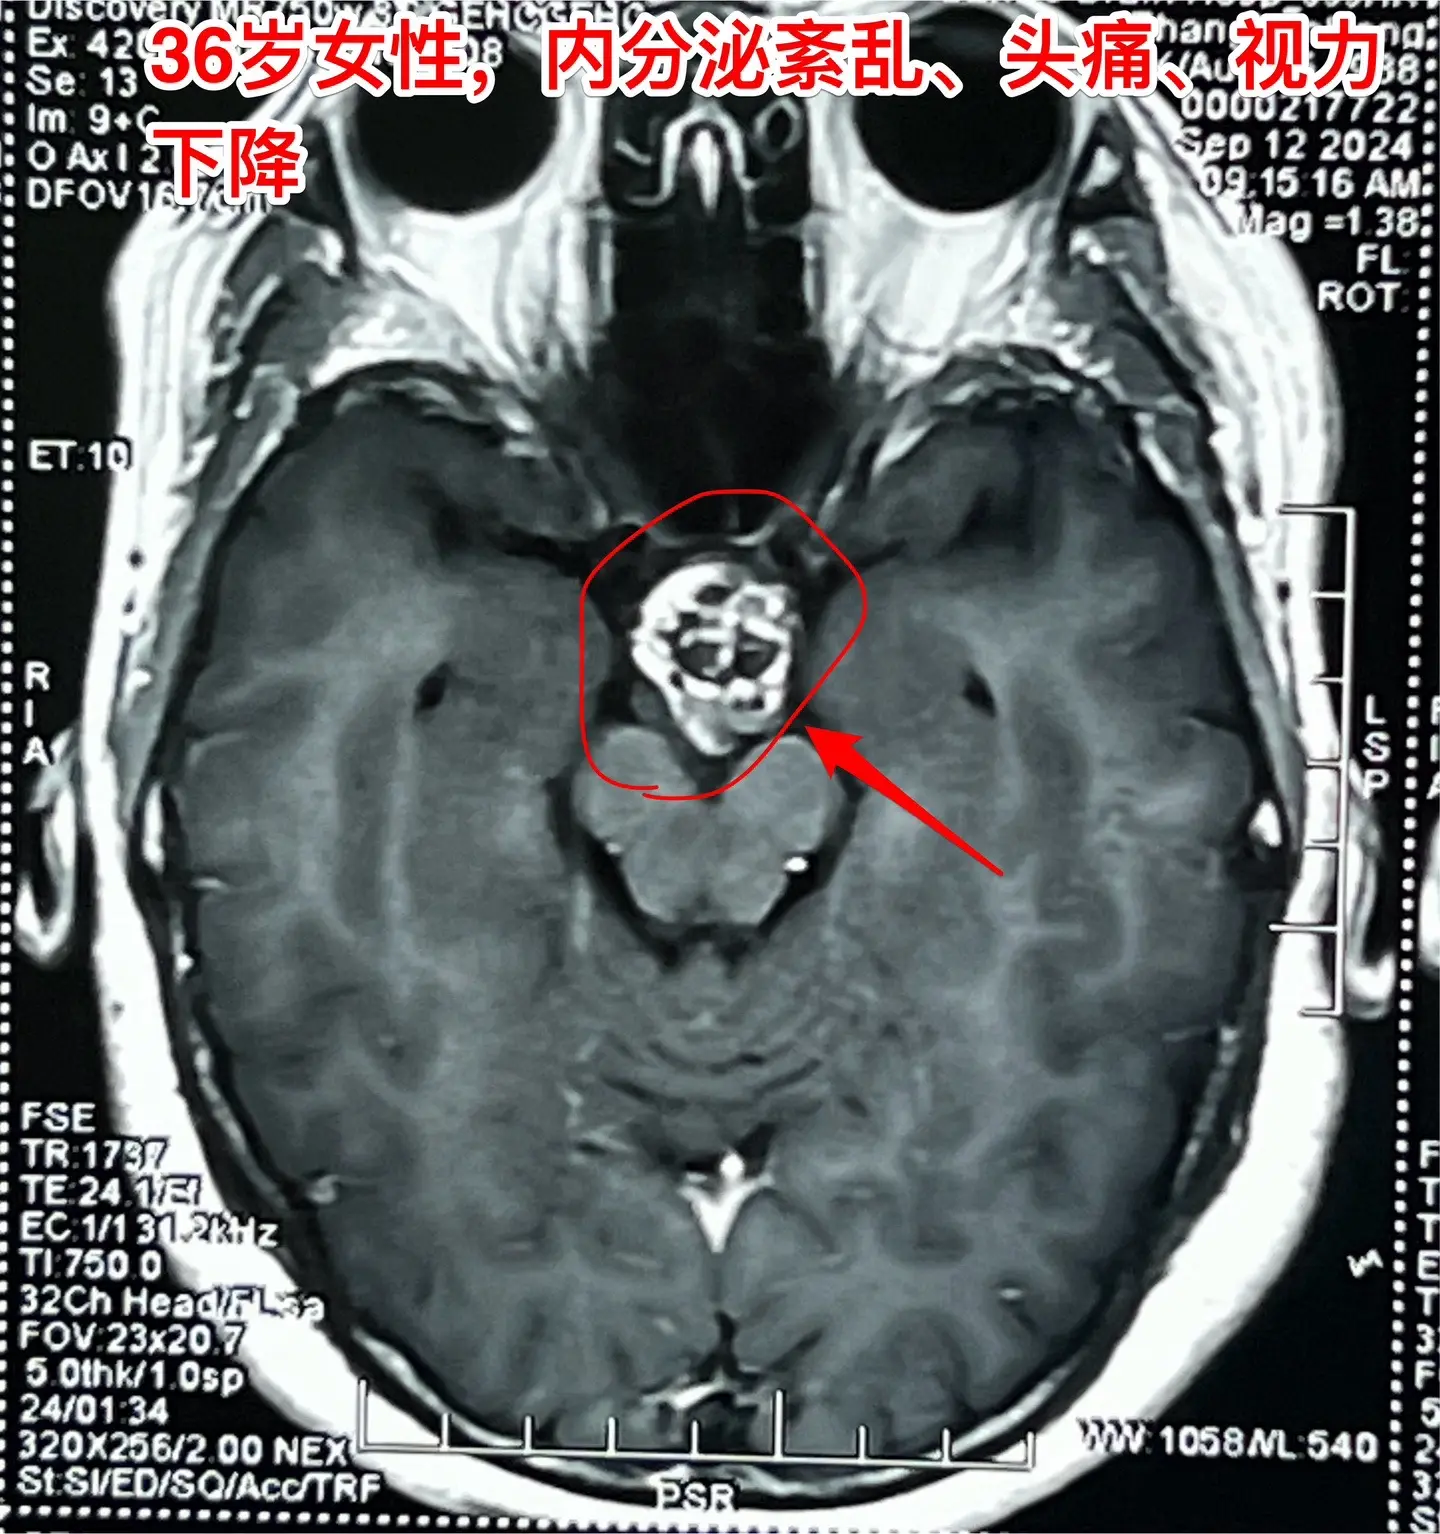

36岁玉溪市女性,颅咽管瘤手术后视力改善。一开始出现内分泌紊乱,随后出现头痛、视力下降。发现颅咽管瘤后于9月11日到我科住院,因为发烧,等到9月24日才作了手术。 好饭不怕晚!手术很顺利,肿瘤得到完全切除,垂体柄保留了30%。手术后病人的身体恢复很快,视力也好转了。